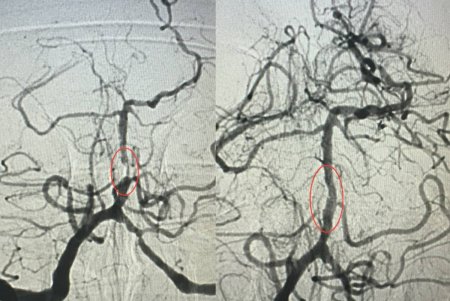

Як розповів завідувач рентгенендоваскулярного блока лікарні Олександр Скрипка, це був один з найскладніших випадків - ураження стовбурової частини мозку. Базилярна артерія була майже повністю закрита атеросклеротичною бляшкою. Такі інсульти належать до найбільш небезпечних, а за відсутності термінової допомоги навіть шанси на виживання мінімальні.

Фахівці прийняли рішення оперувати та провести ангіопластику артерії. Кластерна лікарня №10 має досвід такої методики лікування в кардіології при атеросклерозі коронарних судин, але застосування її для мозкових судин - це інноваційна технологія в масштабах України.

Операція тривала близько 60 хвилин. Звужену артерію розширили за допомогою спеціального балона, а потім застосували балон з лікарським покриттям.